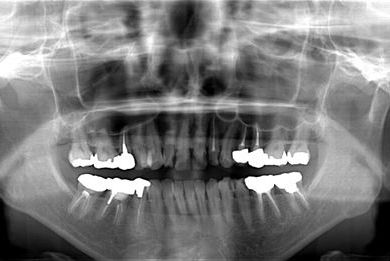

| 主訴 | 痛む歯を治療し、セラミックの歯にしたい。 | ||||||||||||||||||||||||||||||||

| 治療内容 | メタルボンドセラミック2本(メタルボンドセラミッククラウン用の土台2本)、ハイブリッドセラミックインレー2本 | ||||||||||||||||||||||||||||||||

| 総治療費 | 344,821円 | ||||||||||||||||||||||||||||||||

| 治療期間 | 11ヶ月 |